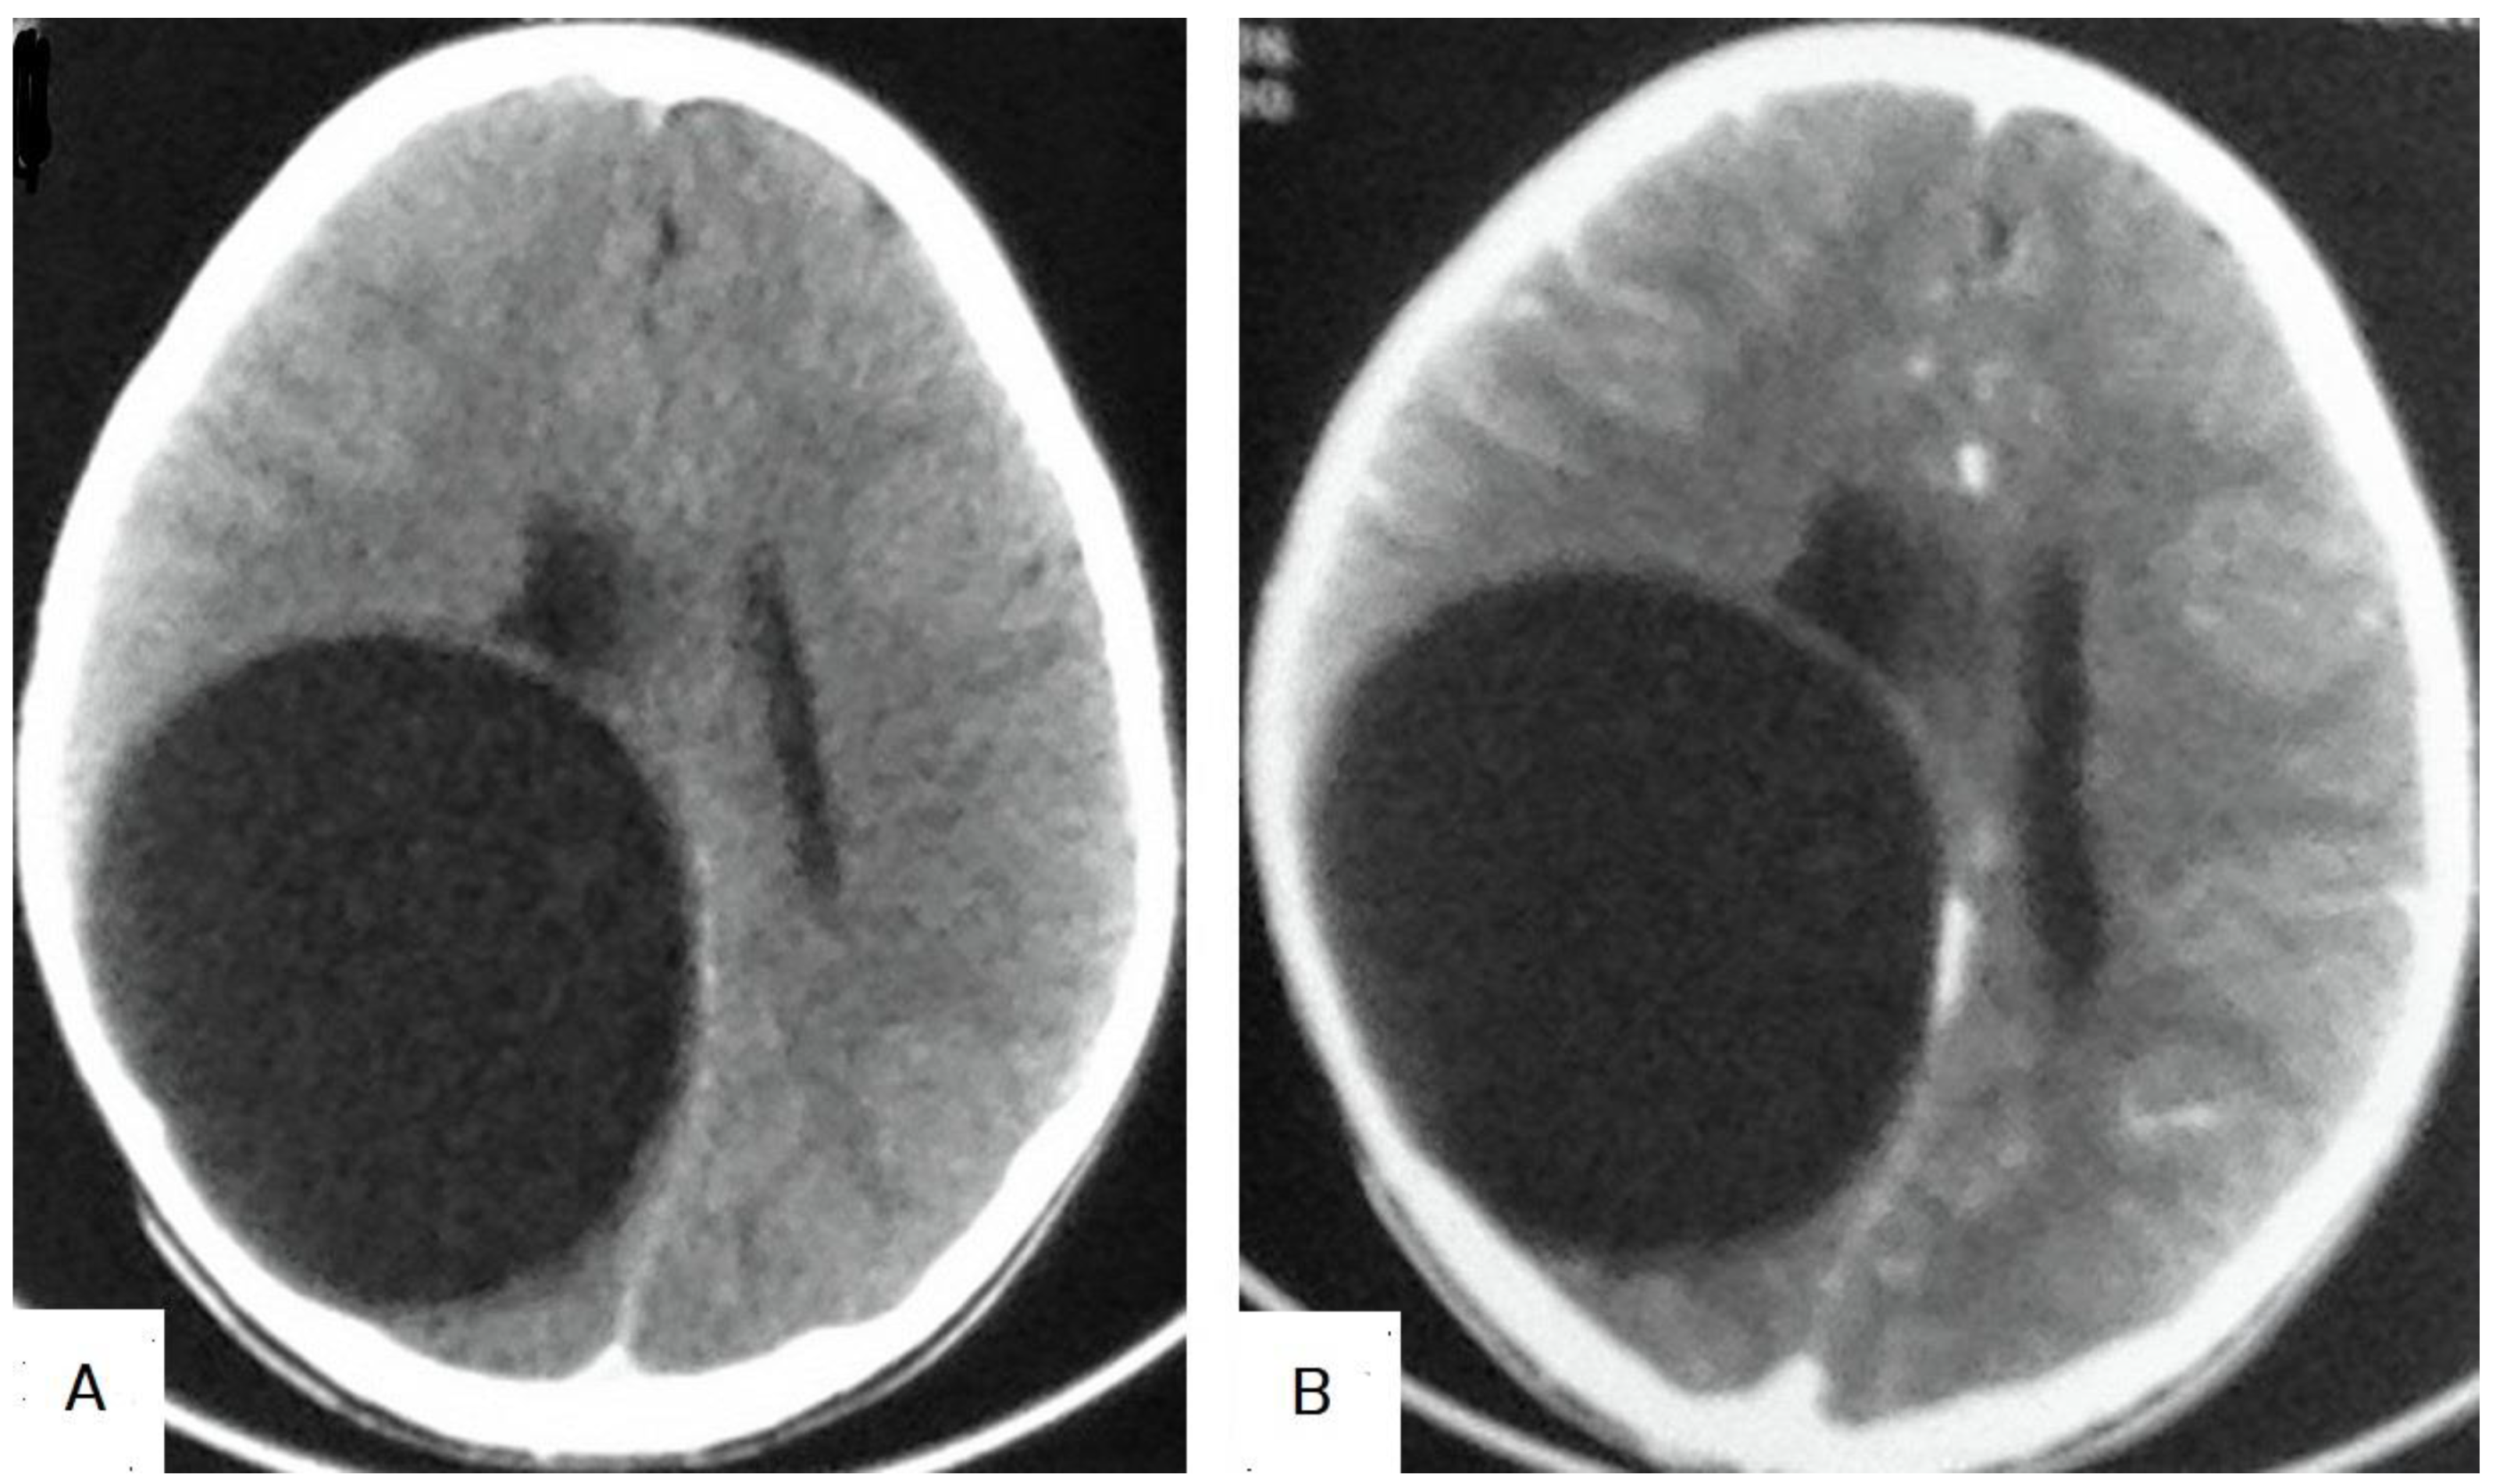

5.4. Hydatid Cysts of the Brain

| Abbasi et al. [39] Agrawal et al. [41] | Brain hydatid cysts can mimic brain cystic lesions, such as the following: 1: Arachnoid cysts. 2: Porencephalic cysts. 3: Pyogenic abscesses. 4: Cystic tumors of the brain. 5-Neurocysticercosis. |

| Ganjeifar et al. [42] | Brain hydatid cysts can mimic brain lesions, such as the following: 1: Pyogenic abscesses. 2: Granulomas. 3: Cystic gliomas. 4: Epidermoid cysts. 5: Arachnoid cysts. |